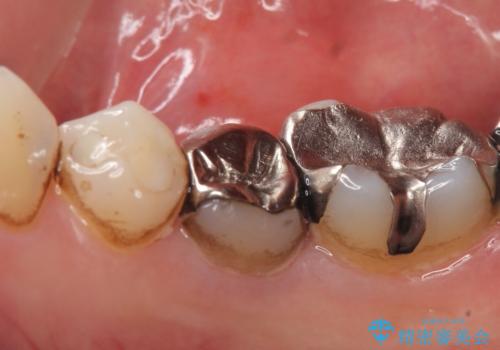

- 右下の歯でものを咬むと違和感があるので診て欲しいといらっしゃった方の症例です。

右下5番目の歯に根尖病変を認めたため、再根管治療を行い、オールセラミッククラウンによる補綴を行いました。